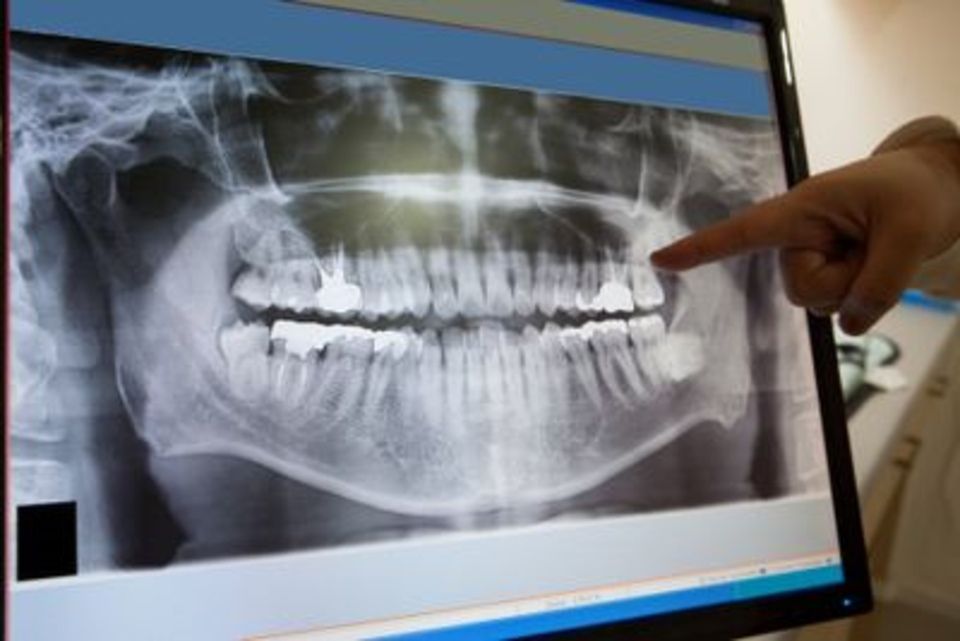

Eseguiamo radiografie dentarie, come ortopantomografia e teleradiografia del cranio, spesso necessarie per pianificare chirurgie orale e altri interventi. Siamo particolarmente apprezzati per la nostra capacità di fornire radiografie dello scheletro per la valutazione di patologie sistemiche, urografia, clisma opaco e RX toracico, dell’esofago, dello stomaco e del duodeno.